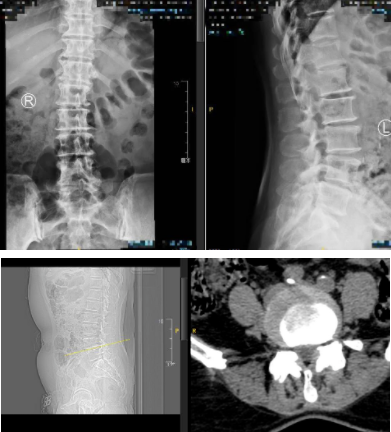

术前

这下可把李阿姨吓得不轻,为求进一步治疗,李阿姨赶紧来到sararz脊柱外科寻求帮助。来到我院后,经医生检查并结合相关片子判断,李阿姨存在腰椎滑脱、腰椎间盘突出、腰椎椎管狭窄等多项问题。